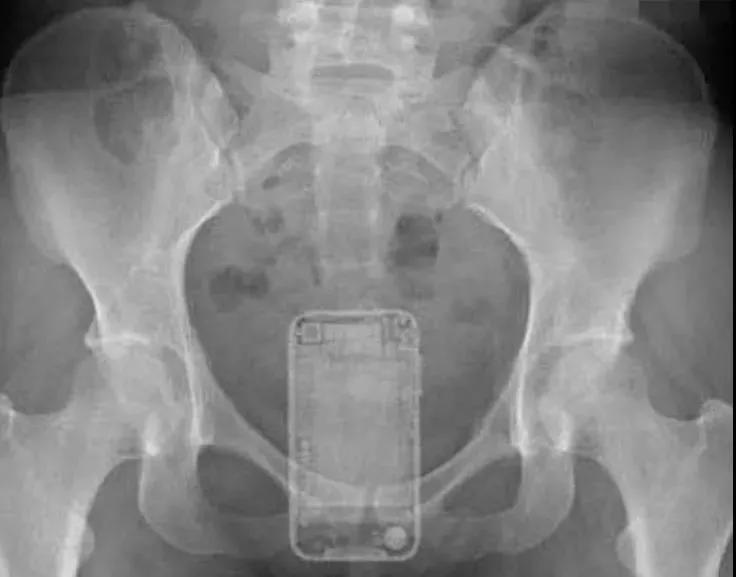

甚至还有手机,千奇百怪

西南医科大学附属中医医院肛肠科主任李五生教授说:直肠异物是直肠里出现除了粪便以外的其他东西,比如灯泡、按摩棒、玻璃药瓶、陀螺、蜡烛、圆柱形金属瓶等等,甚至常见的蔬菜和长条状的物体,比如黄瓜、火腿肠、茄子、苦瓜、黄鳝、泥鳅……